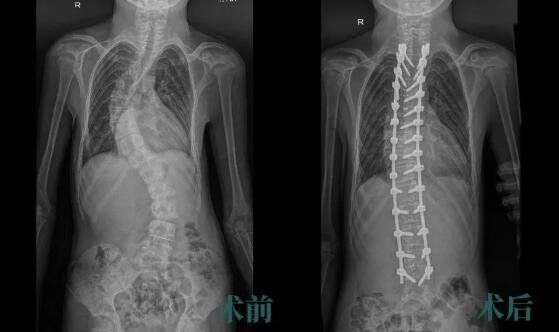

小俊脊柱畸形术后得到了明显的纠正

完善术前准备,在麻醉科和神经电生理监测医护等的精心配合下,朱晓东教授全程指导,尚军主任医师、孟磊副主任医师组成的手术团队顺利完成手术,用时约2小时40分。

术后,为取得更好的矫形效果,脊柱外科医护团队联合康复科帮助小俊进行快速康复、肢体功能锻炼等治疗。一周后,小俊即可佩戴胸腰支具下地活动。

沉重的‘罗锅’不到3个小时就‘卸掉’了!小俊重新“挺直腰杆”,还意外收获约5cm的身高,等待他的将是美好的未来。